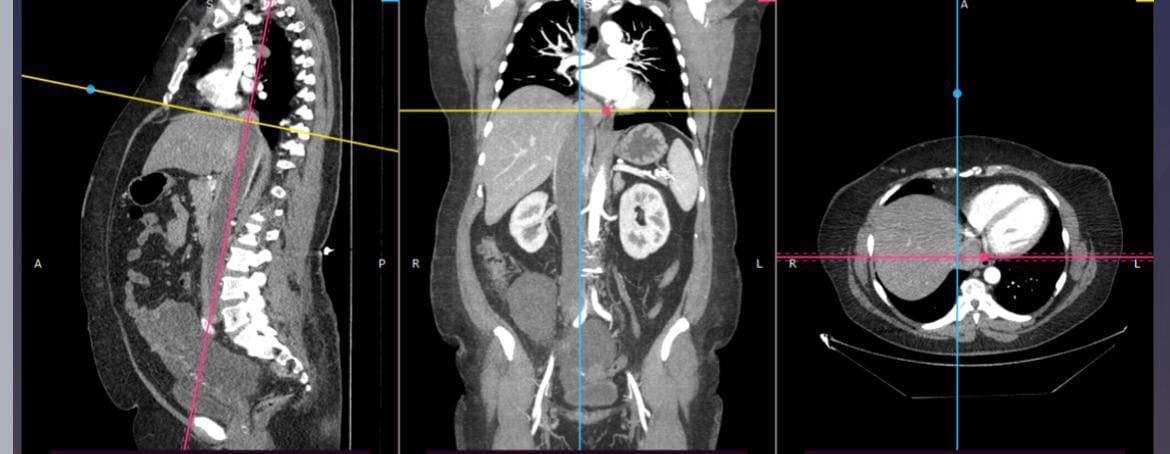

Мешканка Яворівського району звернулася до лікарів після раптової слабкості та потемніння в очах. Під час обстеження у неї виявили тромб, згодом її скерували до Львова, де діагностували новоутвір у матці та тромбоз нижньої порожнистої вени, що доходив до серця.

Під час втручання хірурги видалили матку разом із пухлиною, а також пухлинний тромб довжиною близько 40 см, який сягав правого передсердя. Для безпеки до операції залучили кардіохірурга, який контролював ділянку впадіння вени в серце.

Дослідження показали, що у пацієнтки була лейоміома — доброякісна пухлина матки. Водночас випадки її поширення у порожнисту вену є рідкісними і трапляються лише у 0,25–0,4% пацієнток. Після операції жінка повернулася до звичного життя та перебуває під наглядом лікарів.